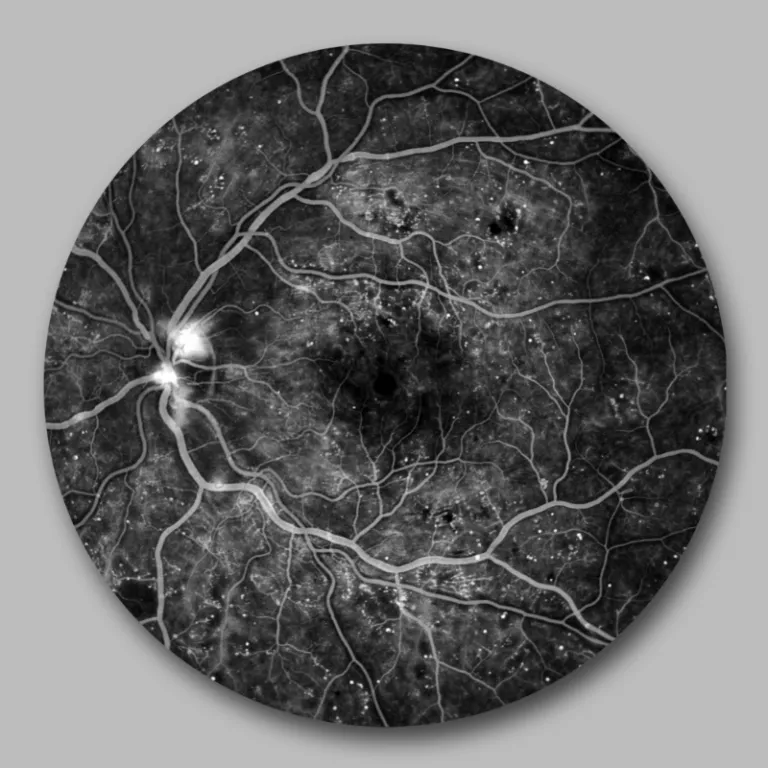

Angiographie der Netzhautgefäße mit Darstellung von neugebildeten Gefäßen am Sehnervenkopf

Zeigen sich Bildungen neuer instabiler Gefäße, so handelt es sich um eine proliferative Retinopathie. Diese Neubildungen führen zu Einblutungen sowohl in die Netzhaut als auch den Glaskörperraum, wodurch das Sehen – je nach Blutmenge – eingeschränkt wird.

Die Netzhaut wird aufgrund der diabetischen Gefäßveränderungen stellenweise schlecht mit Sauerstoff und Nährstoffen versorgt. Dadurch werden bestimmte Wachstumsfaktoren (VEGF) ausgeschüttet, die zur Bildung neuer Gefäße führen.